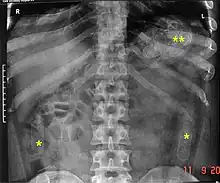

X-ray diagnostic images can reveal concealed contraband that could not otherwise be detected. The yellow marks show capsules of illegal drugs swallowed by the suspect. Such smugglers are often called drug packers or mules.